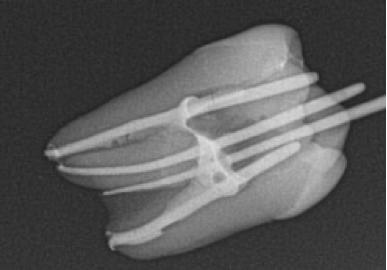

Treatment of fine canals

Dickon Adams presents a case study focusing on severe pain in the UL6. Patient complaint The 43-year-old patient attended with…

Endodontics